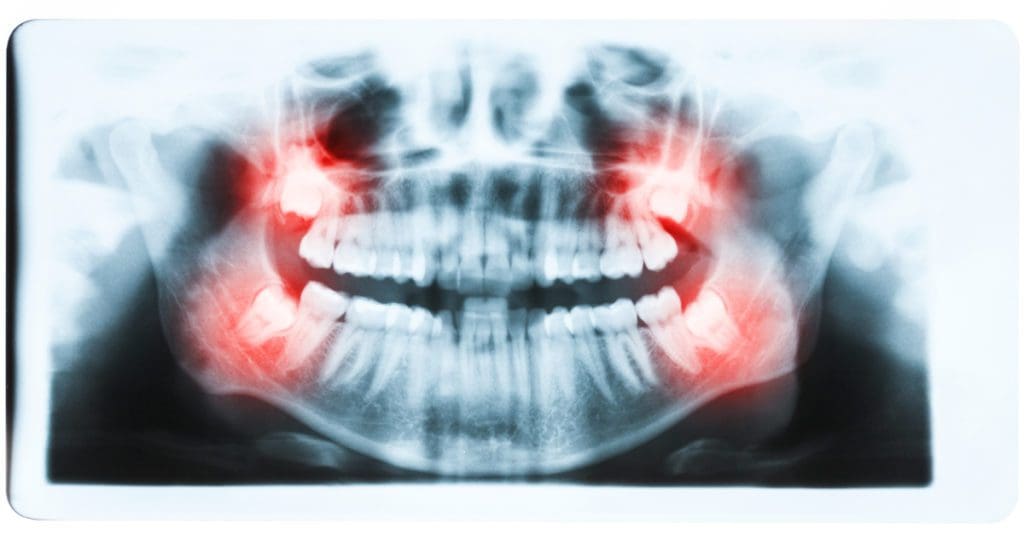

Impacted Tooth? Symptoms, Treatment, Removal

Do you think you have an impacted tooth? Wisdom teeth sound like something that we made up. But there are teeth in our mouth with that moniker. We call them “wisdom teeth” because they mark the transition between childhood and adulthood. You are supposed to gain wisdom as you mature. However, wisdom teeth can cause […]